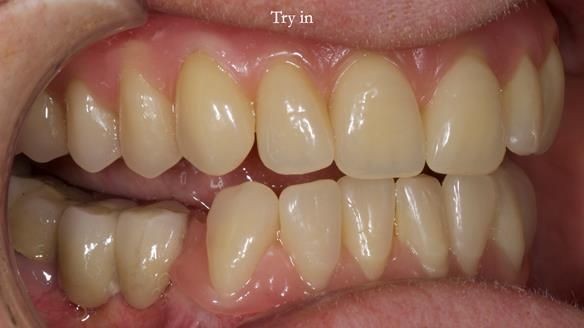

However, once Rowan and I reviewed the remaining metal crown on tooth 46, we realised it would make an ideal abutment for a gasket denture. By reshaping the lingual surface of the crown, we created an excellent gasket seal.

This approach worked far better than the proposed ring-clasp design - improving retention, comfort, and aesthetics while keeping the design clean and simple.

- The gasket seal around 46 was made using retention.sil 200, producing a precise, cushioned fit.